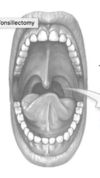

What is this organ called (spell)?

What is the removal of this organ called? (spell)?

Tonsillectomy is a surgery to remove the tonsils.

Right and left tonsil